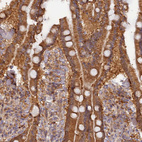

Immunohistochemical staining of human placenta shows strong cytoplasmic positivity in trophoblastic cells.